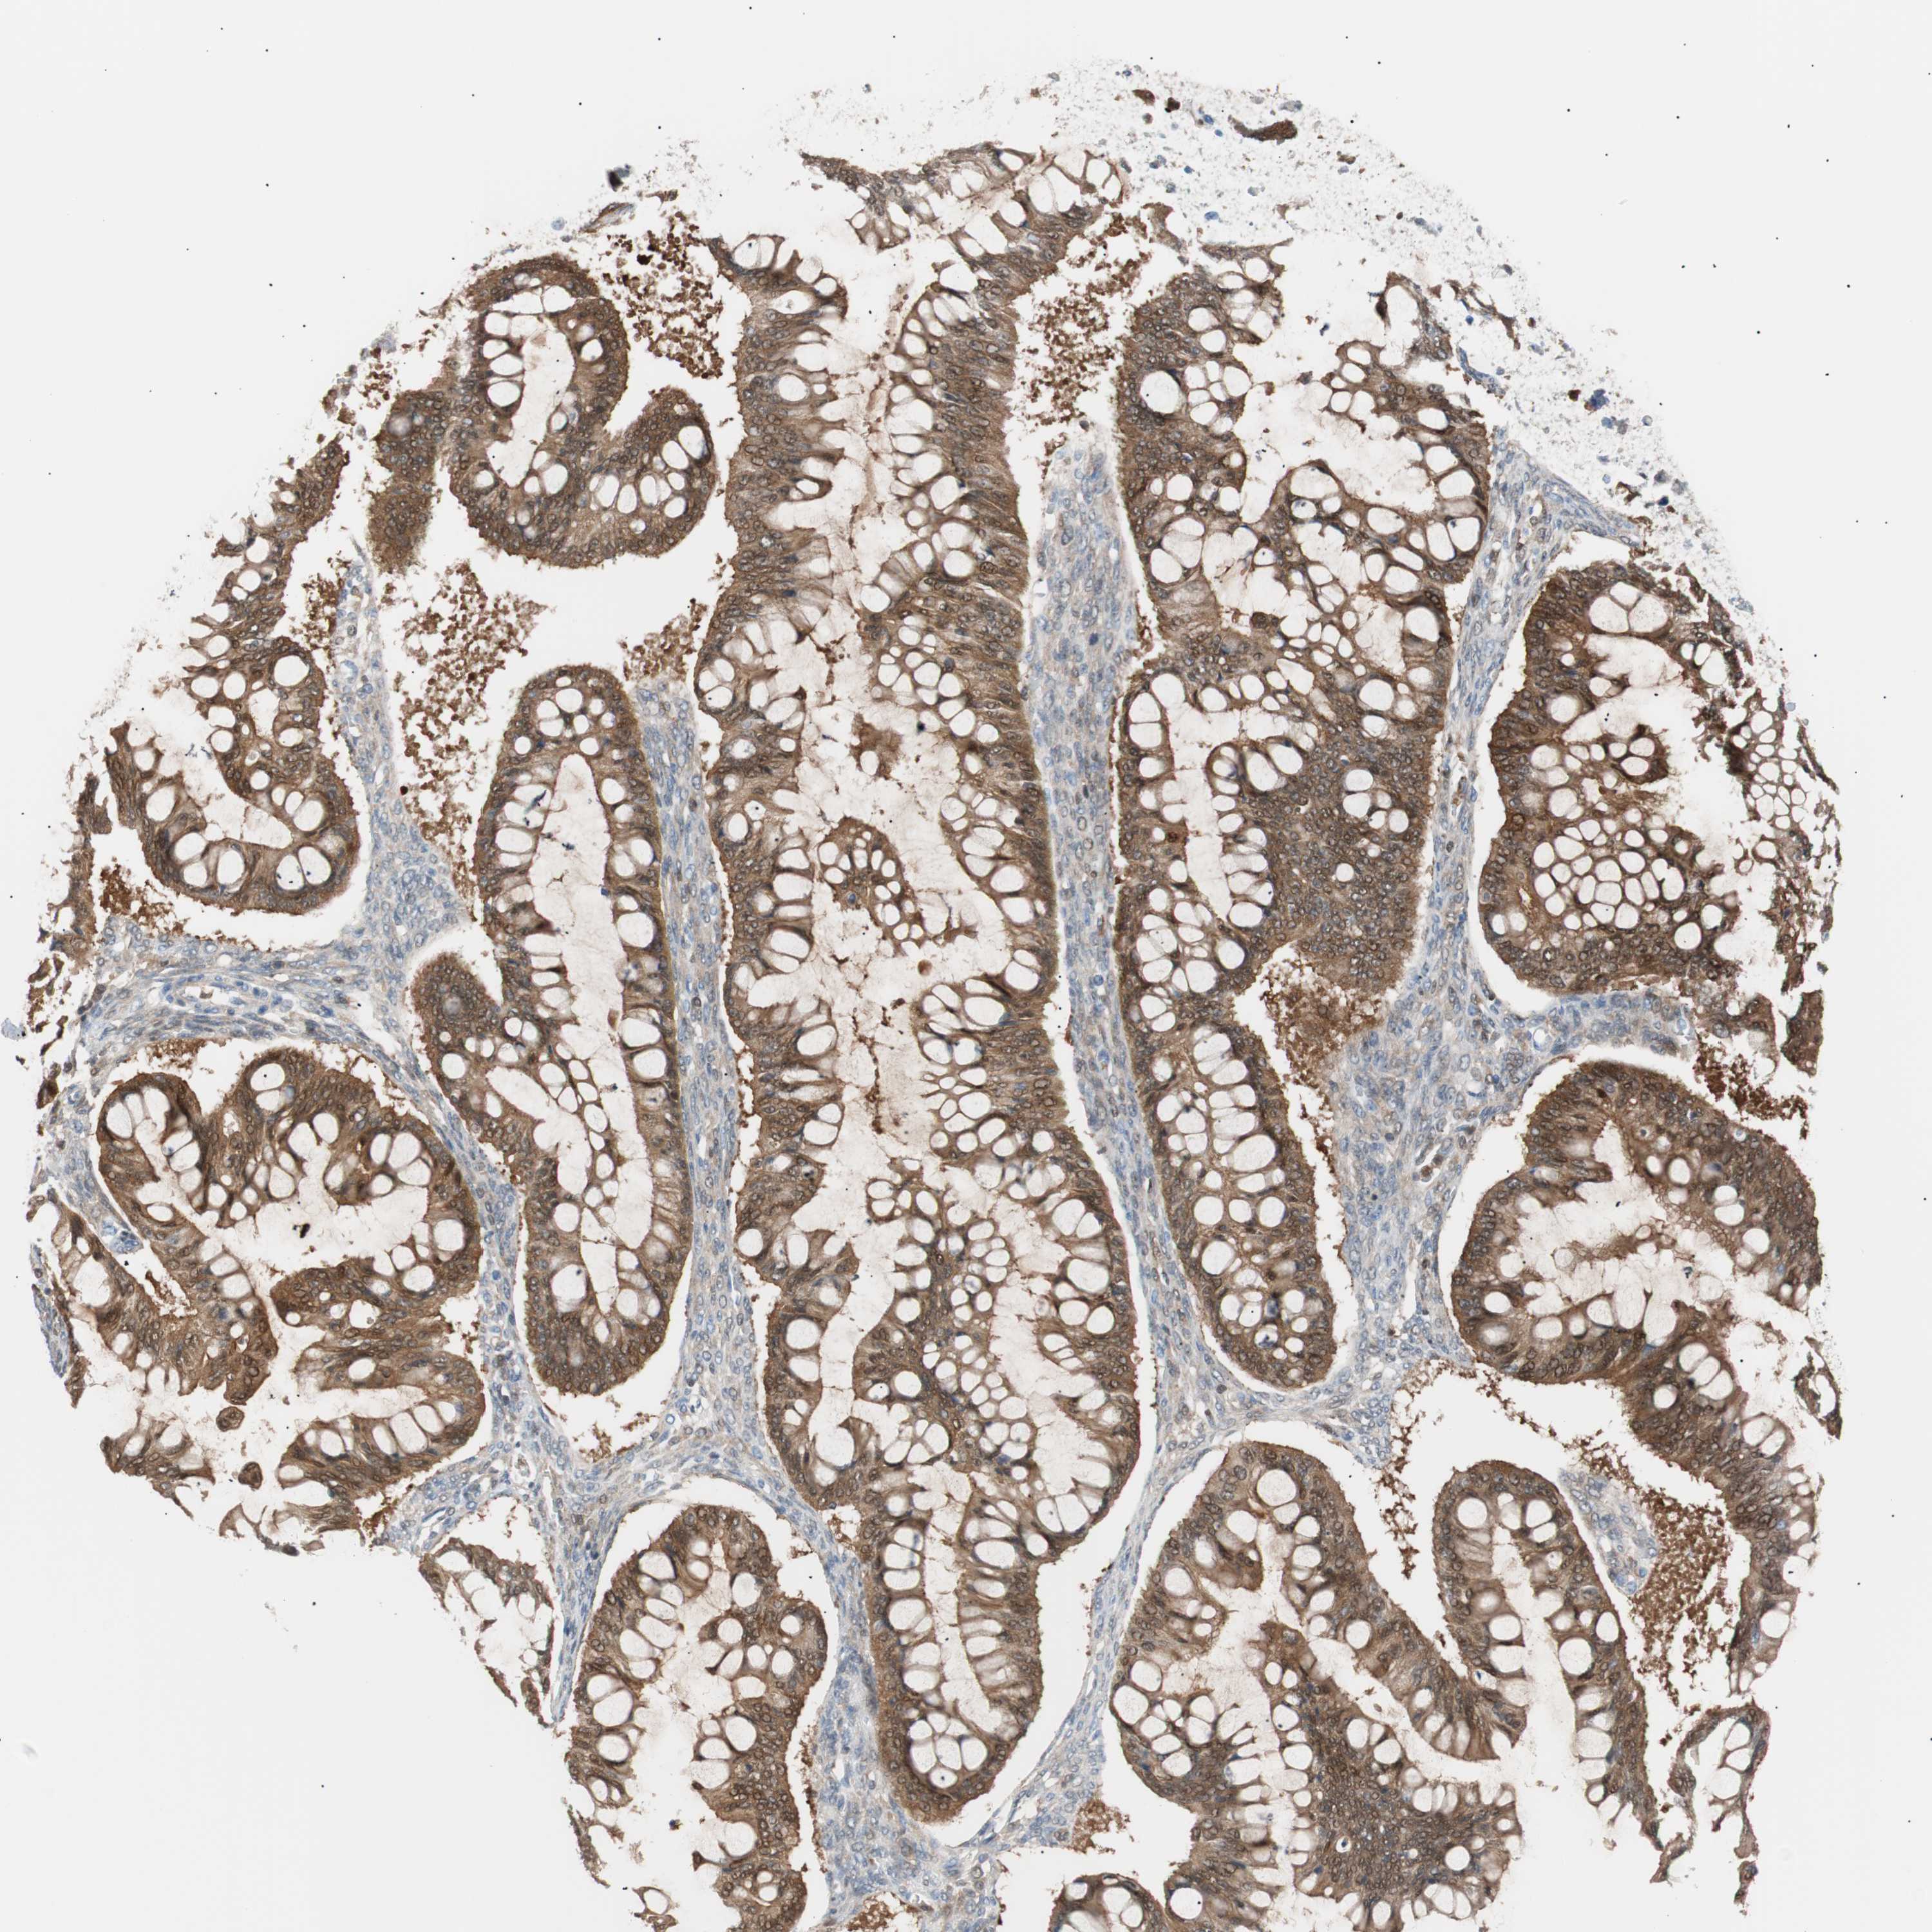

OVARIAN CANCER - Protein expressioni

A mouse-over function shows sample information and annotation data. Click on an image to view it in a full screen mode. Samples can be filtered based on level of antibody staining by selecting one or several of the following categories: high, medium, low and not detected. The assay and annotation is described here.

Note that samples used for immunohistochemistry by the Human Protein Atlas do not correspond to samples in the TCGA dataset.

Antibody stainingi

Antibody staining in the annotated cell types in the current human tissue is reported as not detected, low, medium, or high, based on conventional immunohistochemistry profiling in selected tissues. This score is based on the combination of the staining intensity and fraction of stained cells.

Each image is clickable and will lead to virtual microscopy that enables deeper exploration of all samples and also displays staining intensity scores, fraction scores and subcellular localization as well as patient and tissue information for each sample.

Antibody HPA003980

Antibody CAB007772

Staining

High

Medium

Low

Not detected

Intensity

Strong

Moderate

Weak

Negative

Quantity

>75%

75%-25%

<25%

None

Location

Nuclear

Cytoplasmic/membranous

Cytoplasmic/membranous,nuclear

Carcinoma, endometroid

Carcinoma, NOS

Cystadenocarcinoma, serous, NOS

Cystadenocarcinoma, mucinous, NOS